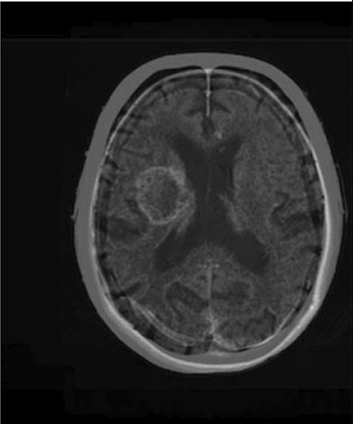

Table 6 Fused image output.

From: Multimodal medical image fusion combining saliency perception and generative adversarial network

Final output